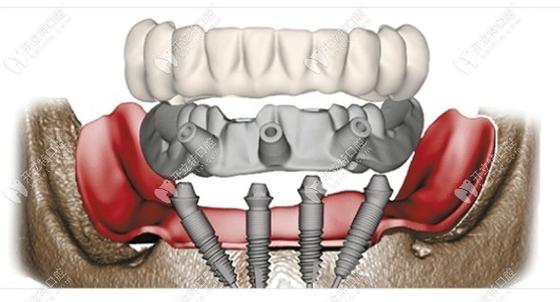

All-on-4种植牙技术作为一种针对半口或全口牙缺失的高效修复方案,通过在颌骨内植入4颗特殊角度的种植体,支撑起整排牙桥,既能快速恢复咀嚼功能,又能避免传统种植中复杂的植骨手术,该技术对患者的条件要求较为严格,需从口腔局部、全身健康状况及个人依从性等多方面综合评估,以确保种植体的长期稳定性和修复效果。

- 骨高度:后牙区种植体需避开上颌窦(上颌)和下牙槽神经管(下颌),通常要求后牙区剩余骨高度≥8-10mm,前牙区≥10-12mm,若骨高度不足,可通过All-on-4特有的倾斜种植体设计(后牙区种植体向远中倾斜45°,避开解剖结构)减少植骨需求,但严重骨缺损(如高度<5mm)仍需结合骨增量手术(如上颌窦提升、骨劈开等)。

解答:并非绝对,All-on-4的核心优势之一是通过倾斜种植体设计,利用现有骨量支撑牙桥,多数骨量不足患者可避免植骨,后牙区骨高度不足时,可将种植体向远中倾斜45°,使其末端避开上颌窦或下牙槽神经,同时利用斜向植入的力学优势增强初期稳定性,但若骨缺损严重(如上颌窦底与牙槽嵴距离<4mm,下颌骨高度<5mm),仍需结合骨增量技术(如上颌窦内提升、骨移植等),否则会增加种植体失败风险,是否植骨需通过CBCT评估,由医生综合判断。